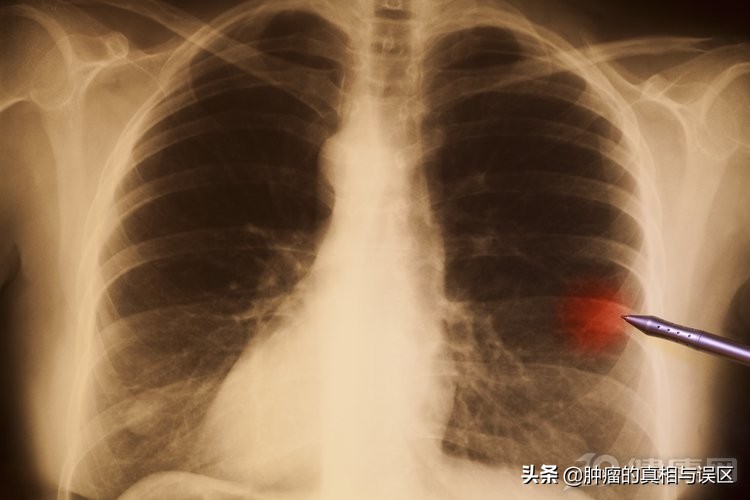

防肺癌:

肺癌早期筛查必须做CT,尤其是“低剂量CT”。“低剂量CT”不是什么新型CT,而是把普通CT的参数调整,比如普通CT辐射量是120,而低剂量CT的辐射量可能只有30,但是其清晰度依然达标。这种检查的辐射量大幅度降低,对人体伤害更小。另外,还可以进行肿瘤标志物检查、痰细胞学检查等。